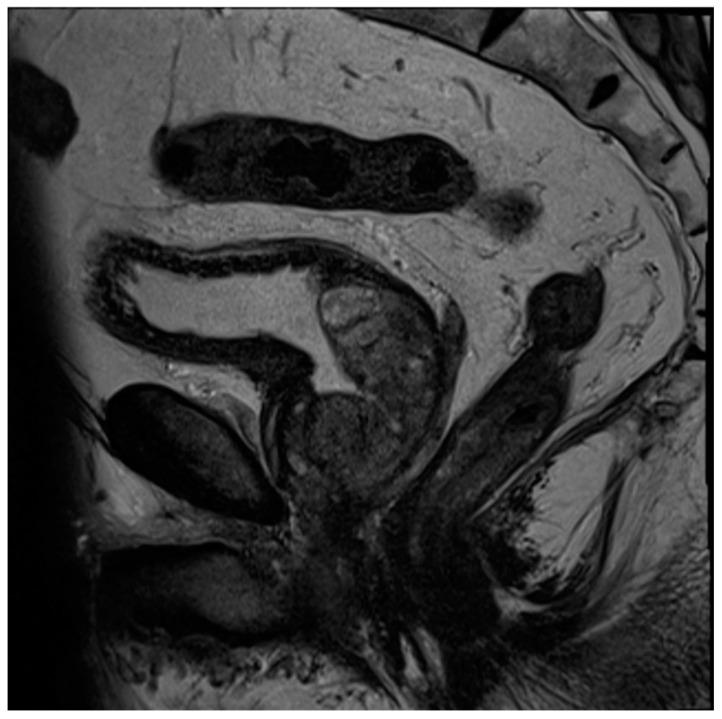

Tissue changes and the enlargement of the prostate, whether benign or malignant, are among the most common groups of diseases that affect men and can have significant impacts on length and quality of life. The prevalence of benign prostatic hyperplasia (BPH) increases significantly with age and affects nearly all men as they grow older. Other than skin cancers, prostate cancer is the most common cancer among men in the United States. Imaging is an essential component in the diagnosis and management of these conditions. Multiple modalities are available for prostate imaging, including several novel imaging modalities that have changed the landscape of prostate imaging in recent years. This review will cover the data relating to commonly used standard-of-care prostate imaging modalities, advances in newer technologies, and newer standards that impact prostate gland imaging.

组织变化以及前列腺肿大,无论良性还是恶性,都是影响男性的最常见疾病类别,会对生活长度和质量产生重大影响。良性前列腺增生(BPH)的患病率随年龄显著增加,几乎所有男性随着年龄增长都会受到影响。除皮肤癌外,前列腺癌是美国男性中最常见的癌症。影像学是这些疾病诊断和管理的重要组成部分。有多种前列腺成像方式可供选择,包括近年来改变了前列腺成像格局的几种新型成像方式。本综述将涵盖与常用的标准护理前列腺成像方式、新技术进展以及影响前列腺成像的新标准相关的数据。